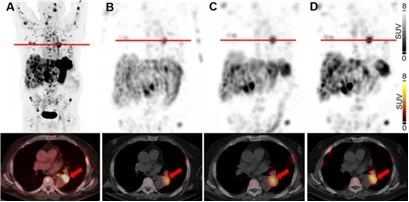

The treatment of patients with advanced medullary thyroid carcinoma (MTC) remains another significant clinical challenge. The cholecystokinin B receptor (CCKBR) has emerged as a promising target for MTC therapy using radiolabeled minigastrin analogs. However, kidney toxicity limits their therapeutic application. In the collaborative study with University Hospital Basel theragnostic suitability of developed by our group radiolabeled minigastrin analog [177Lu]Lu-PP-F11N was evaluated in MTC patients. The first clinical application of [177Lu]Lu-PP-F11N revealed efficient intratumor accumulation by single photon emission computed tomography (SPECT) in MTC patients [Sauter et al., 2018. J Nucl Med]. More recently, high tumor accumulation of metabolically stable radiolabeled minigastrin [177Lu]Lu-PP-F11N was demonstrated in MTC patients with low adverse reactions [Rottenburger et al., 2020. J Nucl Med] (Fig. 9).

Fig 9.

SPECT/CT scans 24 h after 177Lu-PP-F11N injection in MTC patients. (A-C) Tumors are indicated by arrows. Adapted from Rottenburger et al., 2020. J Nucl Med.

Importantly, the compound exhibited a favorable biodistribution profile with low radiation doses to the kidneys and bone marrow, although the stomach was identified as the dose-limiting organ. Currently, further clinical investigations of [¹⁷⁷Lu]-PP-F11N are underway, including combination with other treatment modalities, to improve tumor-specific uptake and therapeutic efficacy in MTC patients.